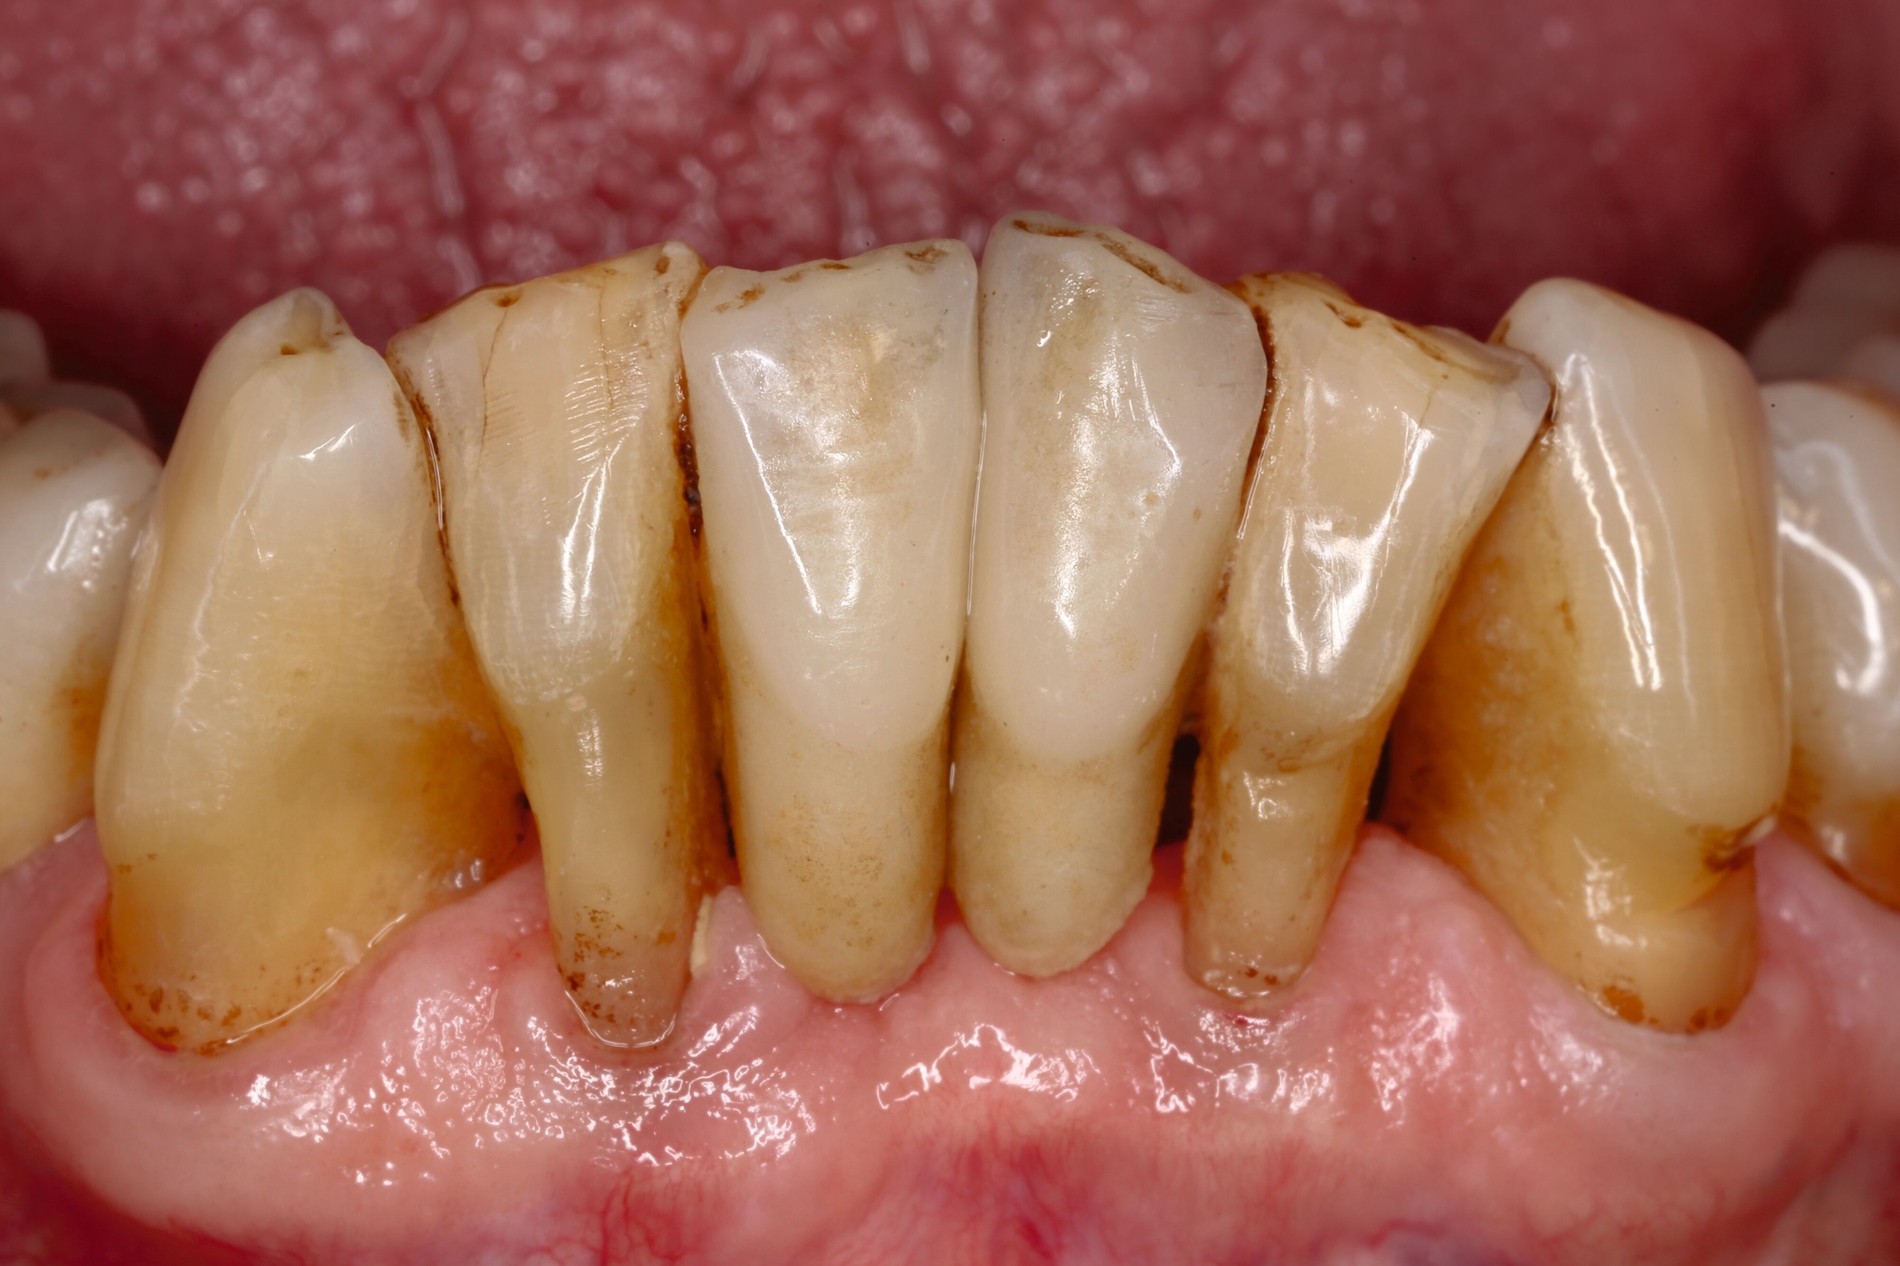

Der Patient wies verkürzte Zahnreihen im Ober- und im Unterkiefer sowie zusätzliche Schaltlücken im Unterkiefer auf (Abbildung 9). Nach Abschluss der ersten beiden Stufen der Therapie (nicht-chirurgische Parodontitistherapie), die darauf abzielte, alle vorhandenen Zähne zu erhalten, wurden an allen Zähnen Sondierungstiefen von maximal vier Millimetern erreicht. Anschließend erfolgte die Planung des definitiven Zahnersatzes im Sinne der aktuellen Leitlinien-Empfehlungen:

Ein Ersatz der Molaren war nicht erforderlich, da der Patient mit der verkürzten Zahnreihe seine Kaufunktion als ausreichend empfand. Aufgrund der erhöhten Beweglichkeit der Oberkieferfrontzähne, die die mundgesundheitsbezogene Lebensqualität stark beeinträchtigte, wurde eine adhäsive Schienung von Zahn 13 bis 21 durchgeführt. Dabei kam ein Polyethylen-Fasernetz (Ribbond, Seattle, USA) zum Einsatz (Abbildung 10). Zur Versorgung der Freiendsituation wurden zwei Implantate mit lokalem Knochenaufbau inseriert und mit implantatverankerten zementierten Einzelkronen versorgt. Die Frontzahnschaltlücke im Unterkiefer wurde mit zwei einflügeligen Adhäsivbrücken aus labial verblendeter 3Y-TZP-Zirkonoxidkeramik (Abbildungen 11 bis 13) geschlossen, die Schaltlücken regio 44 und 46 durch eine Anhängerbrücke, die von Zahn 47 bis Zahn 44 reichte (Abbildung 14).

Der Patient konnte über einen Zeitraum von mehr als 20 Jahren nachbeobachtet werden. In den ersten 14 Jahren stellte er sich jährlich in der Klinik zur unterstützenden Parodontitistherapie und Kontrolle der Restaurationen vor (Abbildung 15). Der parodontale Zustand konnte stabil gehalten werden und auch die prothetischen Versorgungen erwiesen sich komplikationsfrei.

Danach wurde der Klinikbesuch für den inzwischen 83-Jährigen zu beschwerlich, und er wurde von einem wohnortnahen Zahnarzt betreut. Die von ihm 19 Jahre nach Eingliederung des Zahnersatzes angefertigte Panoramaschichtaufnahme dokumentiert die unveränderte prothetische Versorgung des Unterkiefers sowie die stabile Situation der verkürzten Zahnreihe im Oberkiefer (Abbildung 16). Für eine detaillierte Darstellung des Fallberichts wird auf die Originalpublikation verwiesen [Wolfart und Kern, 2024].